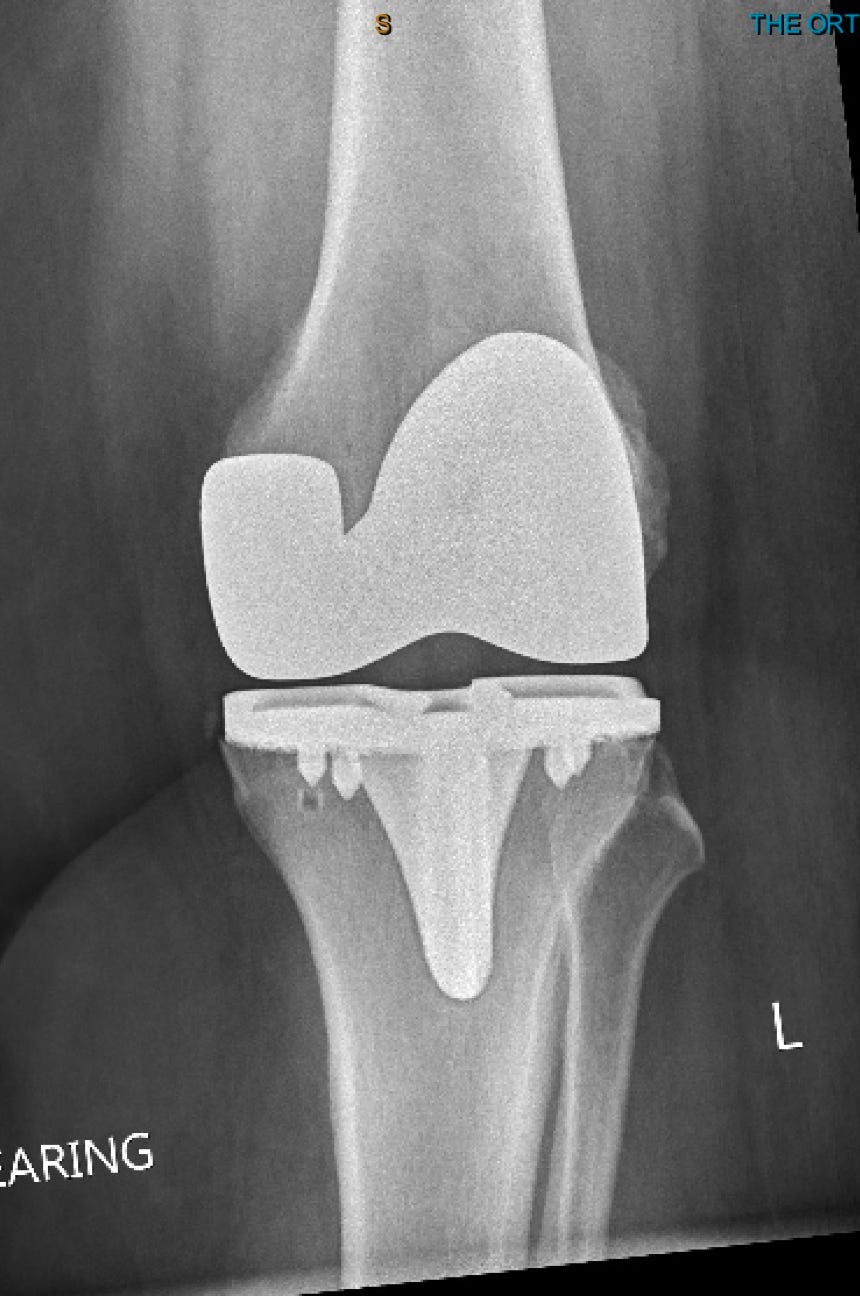

ROBOTIC KNEE REPLACEMENT

Dr. Peterson specializes in Robotic hip and knee replacement. With the use of a robotic arm and specialized sensors, Dr. Peterson is able to perform knee replacement with a higher degree of precision and with less trauma to the muscles and tendons. This allows for less pain and faster recovery, allowing most patients to go home the same day as surgery.